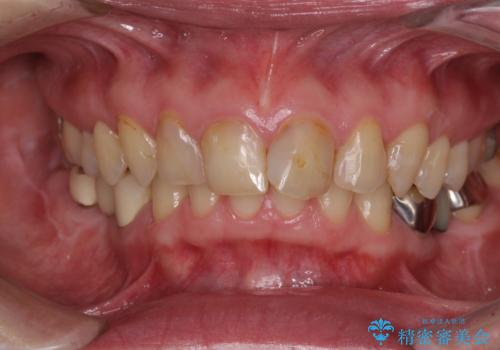

[ セラミック・インプラント全顎治療 ] 長年悩まされている歯の治療にケリをつけたい

![[ セラミック・インプラント全顎治療 ] 長年悩まされている歯の治療にケリをつけたいの症例 治療前](https://seimitsushinbi.jp/wp/wp-content/uploads/2022/01/699ba08b6e311b07f9d2ea9a5b757aea-500x350.jpg?v=1642042101)